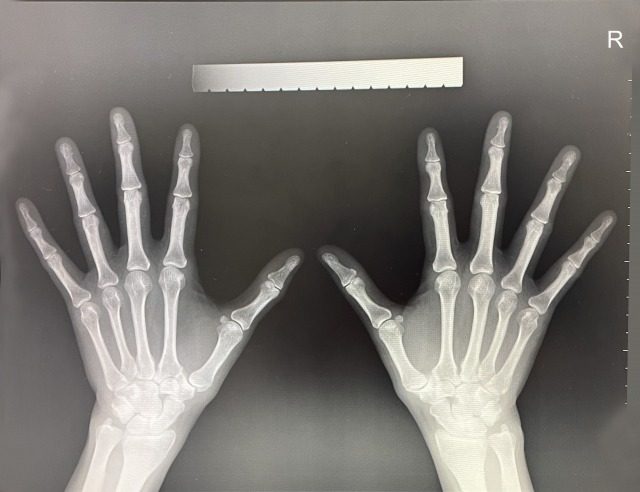

■X線(レントゲン)・MRI・神経伝導検査など、原因を特定する検査

骨の変形や椎間板の状態は、X線撮影(レントゲン)やMRIで確認します。

末梢神経の状態をより詳しく知るために「神経伝導検査」を用いることもあります。

画像検査だけでなく、診察結果と合わせて総合的に判断します。